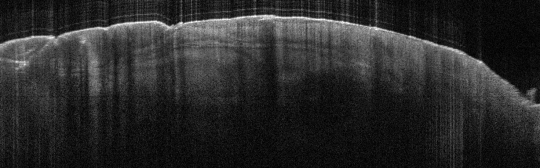

VA9: Left Forearm, Squamous Cell Carcinoma, Invasive